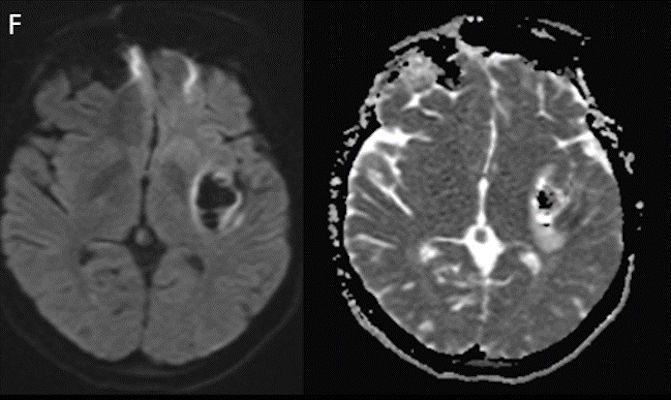

- Difüzyon ağırlıklı görüntülemede (F) difüzyon kısıtlanması izlenmiyor.